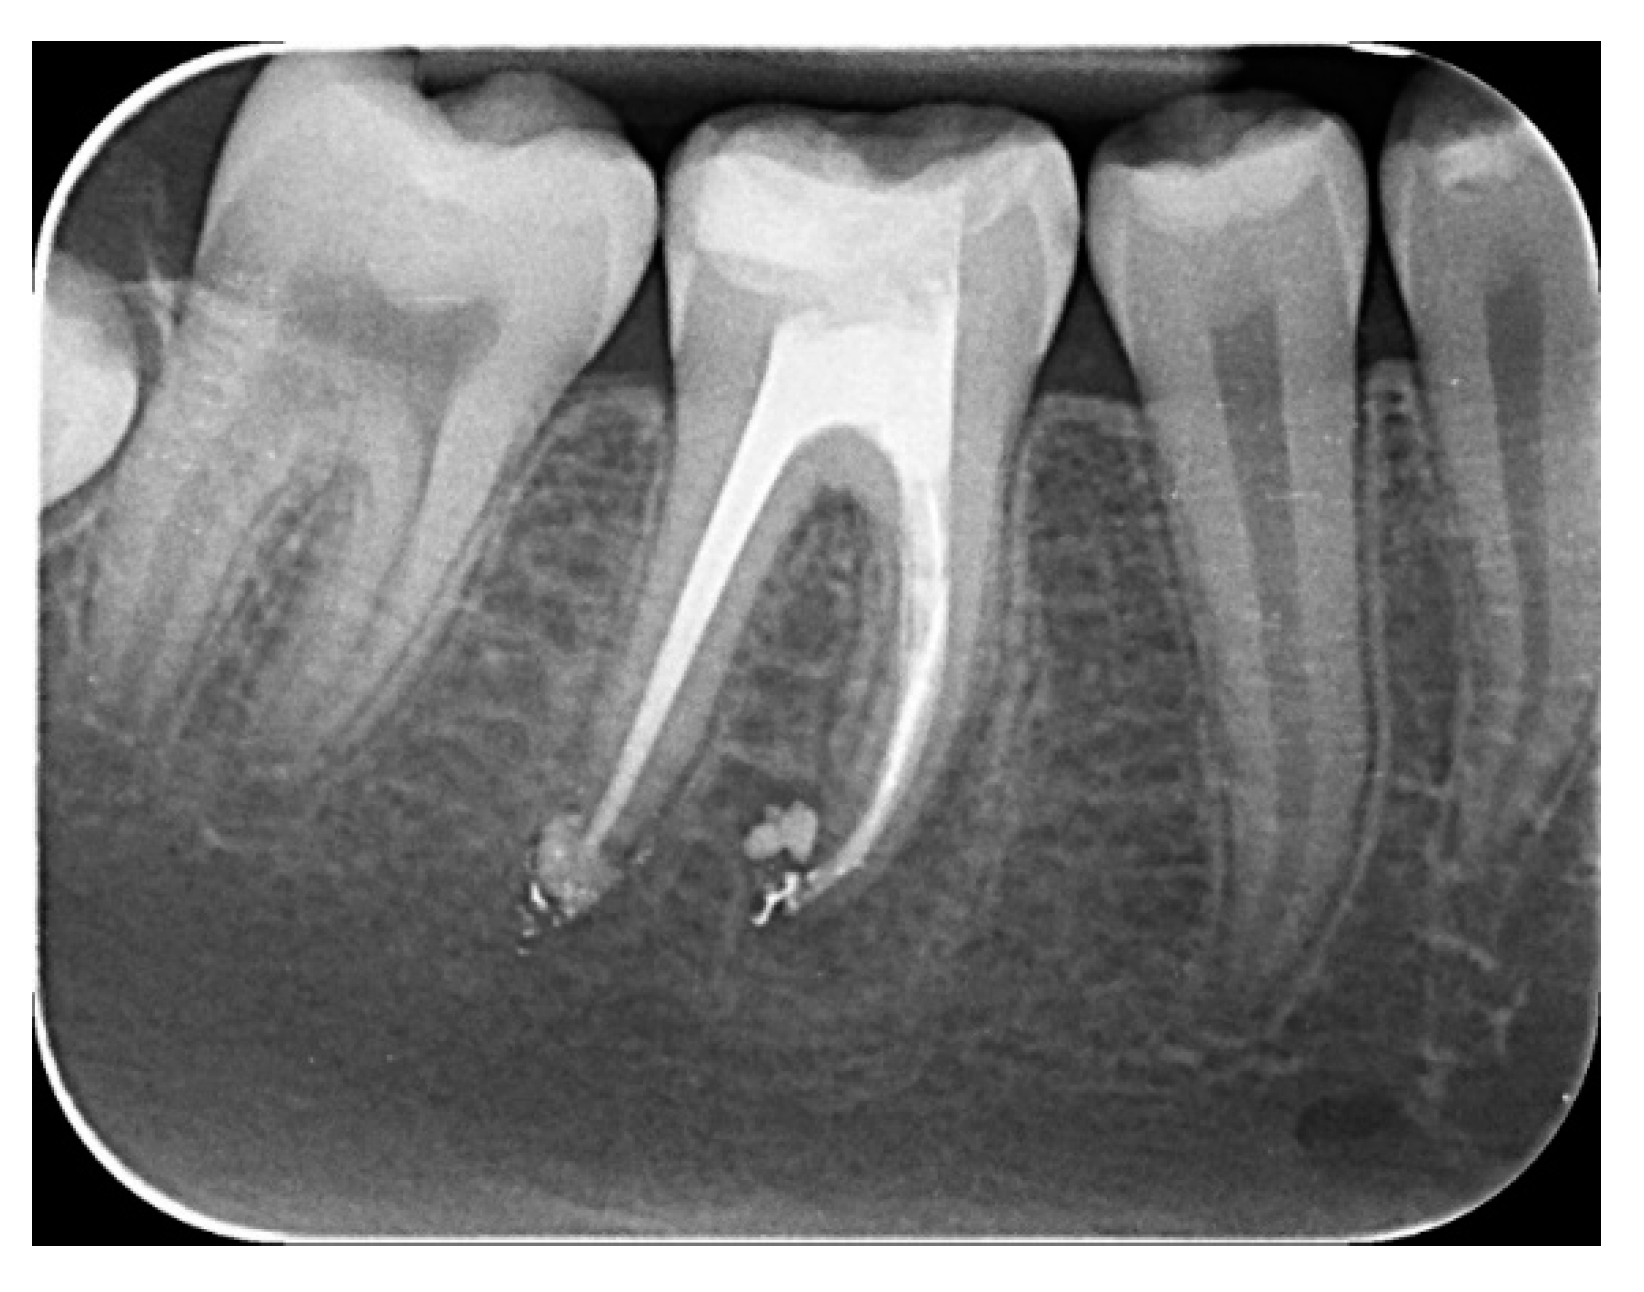

2.2.1. Chemomechanical Debridement of Endodontic Space and Root Canal Filling

2. Materials and Methods

2.1. Study Participant